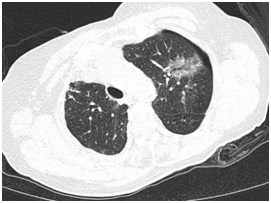

本次接受治疗的是一位82岁高龄患者,既往因右肺癌接受过肺部部分切除手术,此次又发现左上肺19*14mm混合性结节。经北京理工大学附属医院(珠海市人民医院)肺结节专病中心多学科专家会诊,考虑为早期肺癌。由于患者年龄大、既往有肺部手术史,传统外科手术风险较高。经与患者及家属充分沟通并取得同意后,医疗团队决定为其施行机器人引导下的经皮肺结节微波消融术。

手术过程中,机器人一次性精准定位病灶,消融针完美抵达靶区,术后影像显示病灶被完全覆盖。术中患者仅出现少量气胸,生命体征全程平稳,达到预期治疗效果。